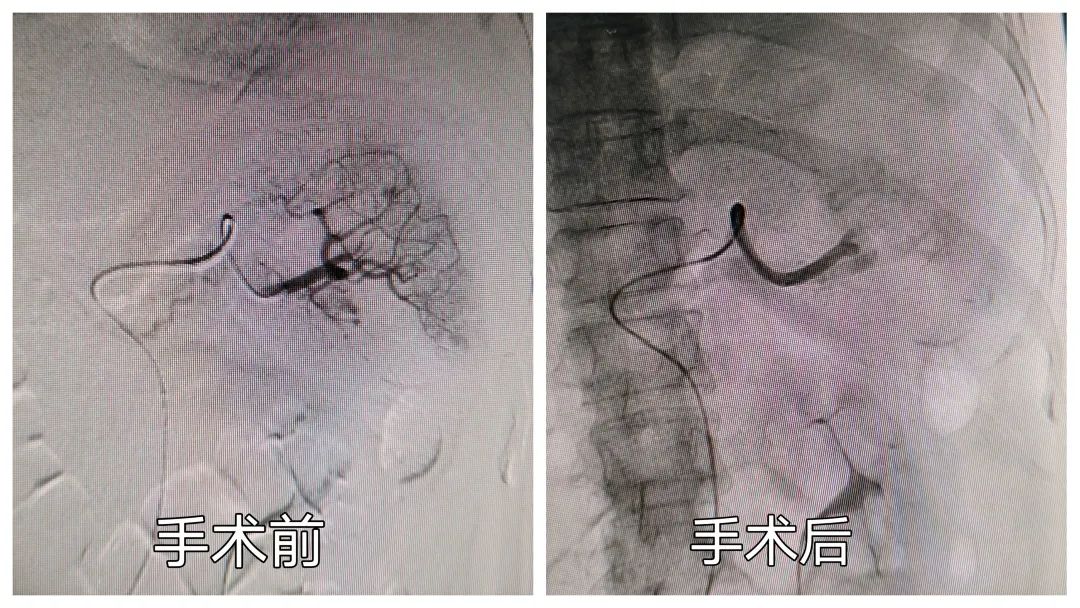

脾破裂,不开刀也能治好?

日前,我院收治一位创伤性脾破裂患者,患者外出时不慎坠落深坑致左侧胸痛明显,急诊入院后行胸腹部CT提示:左侧多发肋骨骨折,腹腔少量积液。入院后主管医生李应甫密切观察患者病情变化,夜间再次急诊复查腹部彩超及腹部CT检查明确诊断:脾脏破裂,腹腔大量积液。李医生立即请示上级医师, 黄剑冰主治医师和夏永立主任认为患者创伤性脾破裂并失血性休克诊断明确,需立即急诊手术。和患者家属充分沟通后,于夜间一点急诊入手术室行经皮穿刺脾动脉栓塞术治疗。选择性血管栓塞治疗不仅挽救了患者生命,还保留了脾脏及脾功能。患者恢复顺利,术后一周复查腹腔积血明显吸收,痊愈出院。

在腹部闭合性损伤中,脾破裂发生率高达20% -42%,脾破裂的处理原则为“抢救生命第一,保脾第二”。常规脾脏切除手术治疗可迅速控制出血,目前仍是治疗外伤性脾破裂的主要方式。但是脾脏切除手术创伤大,术后并发症多,恢复慢,如条件允许尽量保留脾脏。目前对腹腔内实质性脏器出血行选择性血管栓塞治疗已成为大型医疗中心的首选治疗方法之一。其主要优点有局麻、创伤小,治疗精准,能最大限度保留脏器及功能,并发症少,恢复快等优点,目前在国内各大临床医疗中心已广泛开展。